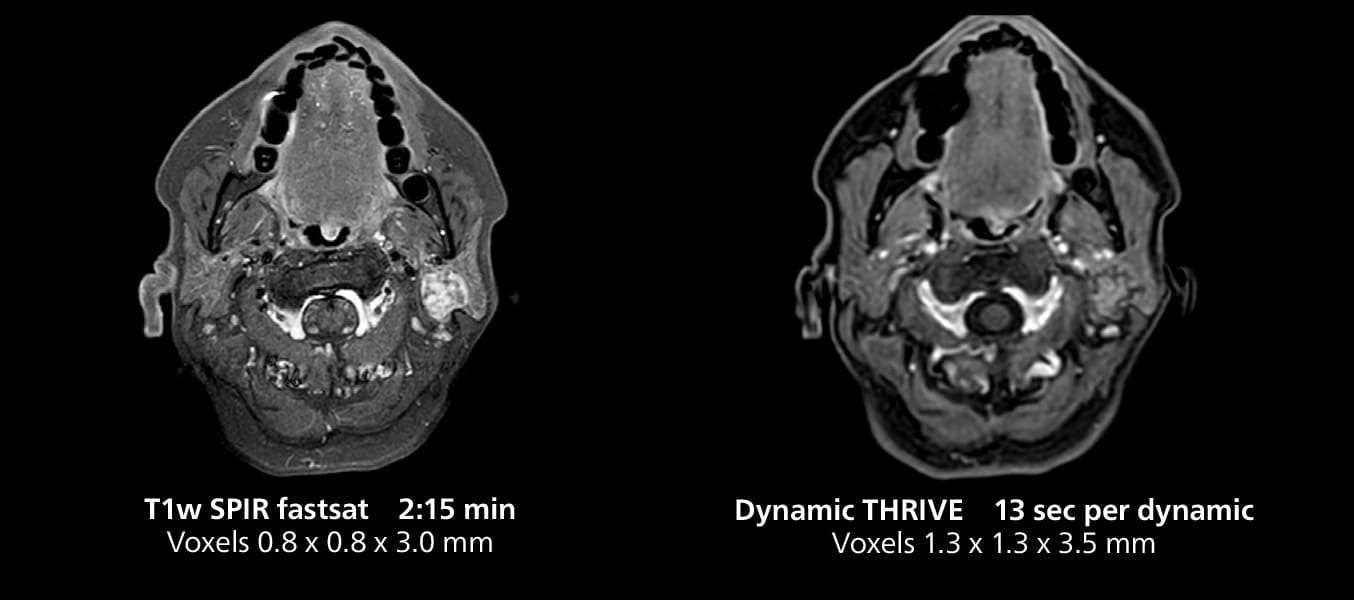

Salivary gland imaging on MR 5300

This MRI case illustrates imaging of salivary gland abnormalities with different sequences. Compressed SENSE allows to accelerate scanning while maintaining high quality. With mDIXON XD, different contrast types can be obtained from scanning one sequence.

Salivary gland imaging on MR 5300

This MRI case illustrates imaging of salivary gland abnormalities with different sequences. Compressed SENSE allows to accelerate scanning while maintaining high quality. With mDIXON XD, different contrast types can be obtained from scanning one sequence.